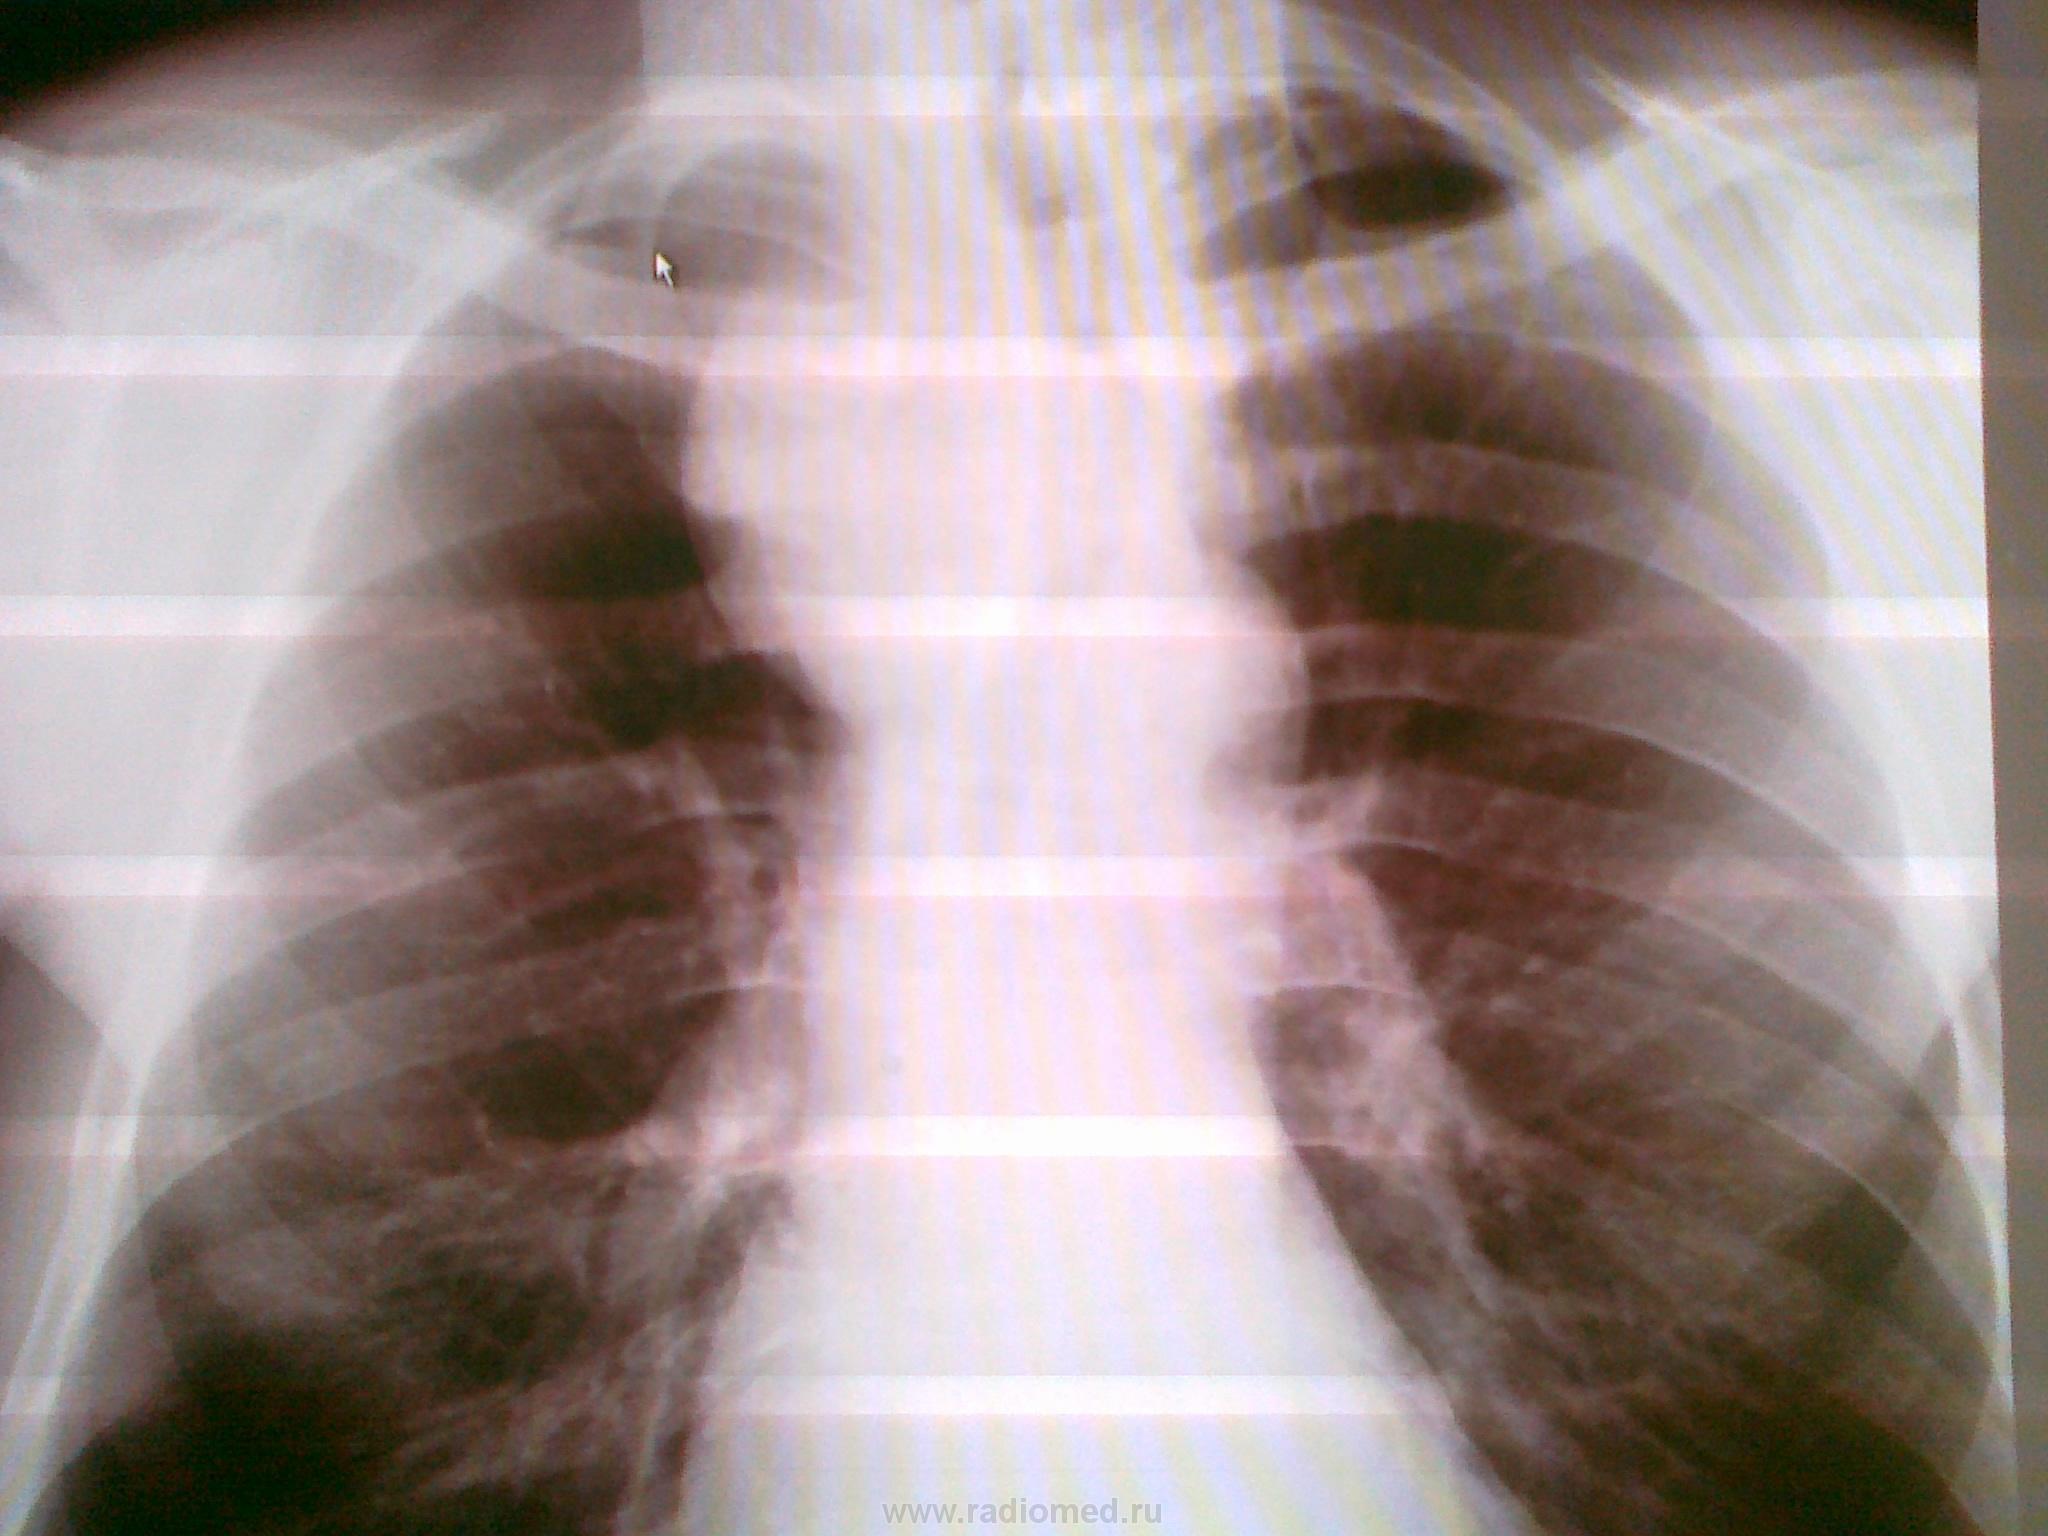

Рис.Слева - обзорная рентгенограмма органов грудной клетки пациента с внутригрудным зобом, по центру - компьтерная томограмма этого же пациента (стрелками указан внутригрудной зоб), справа - сцинтиграфия щитовидной железы у пациента с загрудинным зобом (желтой стрелкой указан холодный загрудинный узел, красной - горячий узел в верхнем полюсе правой доли щитовидной железы)

думаю внутригрудной зоб (бокаловидное расширение верхнего средостения справа за счет об'емного образования с четкими контурами, распространяющееся от заднего к переднему средостению,смещение трахеи;отсутствие признаков поражения лимф узлов)